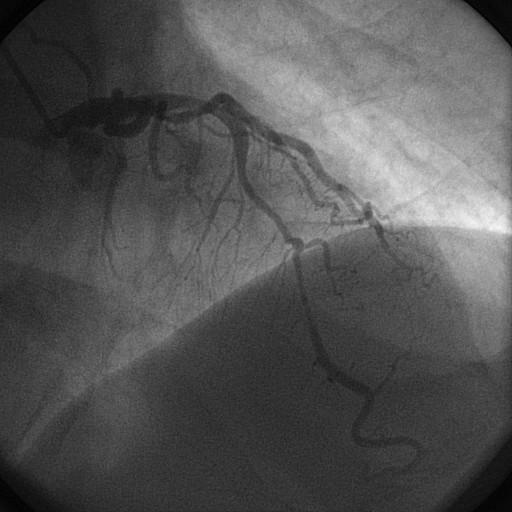

A cinecoronariografia ou angiografia coronariana ainda é considerada o método de imagem padrão-ouro para avaliação da anatomia coronariana. Desde a primeira angioplastia coronariana realizada, a angio…